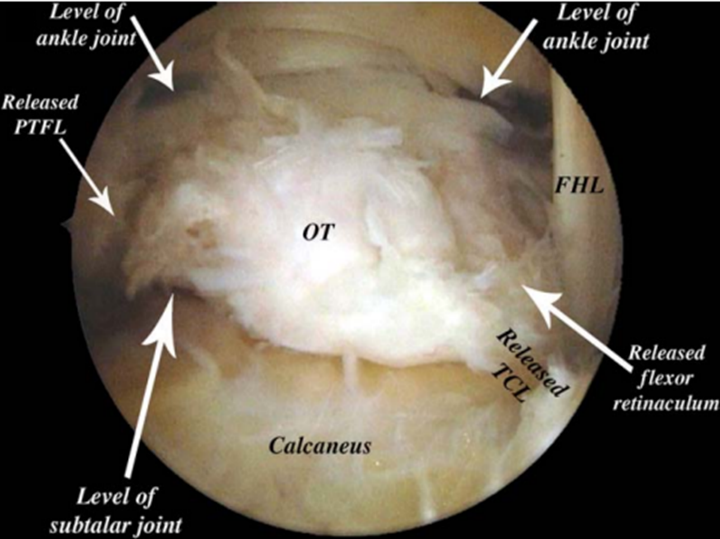

后踝关节镜手术